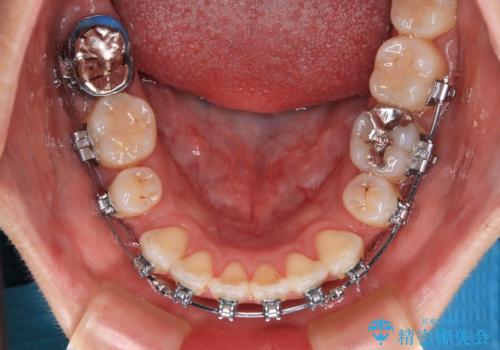

- 矯正装置

- メタルブラケット

- 治療計画

- 上下の出っ歯を気にして来院された患者様です。

口元を積極的に引っ込めるために、上下左右の第一小臼歯を4本抜歯することとしました。

また、上下前歯は舌の突出癖による開咬となっていたため、舌のトレーニングを徹底するよう指示しました。